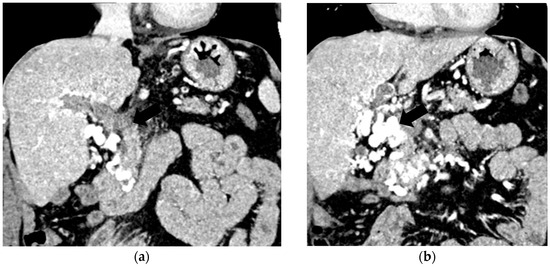

Figure 3.

CT scan in a patient with recent surgery for transverse colon adenocarcinoma. (a) The enlarged portal vein, with intraluminal thrombus and peri-gastric collateral circulation, indicated by black arrow. (b) A 59/34 mm portal cavernoma, indicated by black arrow.

Transabdominal ultrasound with Doppler protocol (Figure 1a,b and Figure 2a,b), CT scan (Figure 3a,b), and MRI (Figure 4a,b) were used for the diagnosis in 88.9, 75.1, and 15% of cases, respectively. CEUS was used for the diagnosis in 49 cases (25.9%) but in only 29 cases was it used for the evaluation of the thrombus, and in two cases for cavernoma diagnosis (Figure 5a,b and Figure 6a,b).